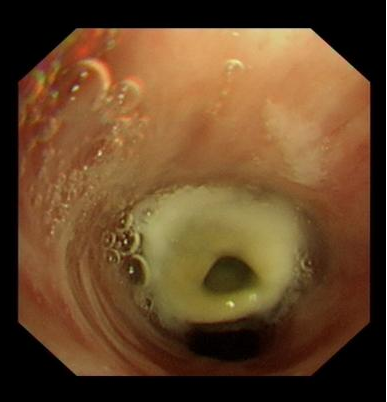

刘奶奶1年前确诊为食管癌,此次因突发呼吸困难紧急入院,经过胸部CT检查,快速找到了刘奶奶呼吸困难的原因,发现患者是因为食道癌压迫引起气道的狭窄。我院呼吸与危重症医学科与麻醉科紧密合作,迅速为患者置入金属覆膜支架。手术效果显著,术后患者气管狭窄问题得到有效缓解,呼吸困难明显改善,患者转危为安,为患者进一步的治疗创造了机会。该技术的顺利开展,不仅迅速解决了患者呼吸困难的问题,提高了患者的生存质量,也展现出呼吸介入团队的卓越能力。我院呼吸与危重症医学科将不断提升专业实力,为更多患者提供更优质的医疗服务。